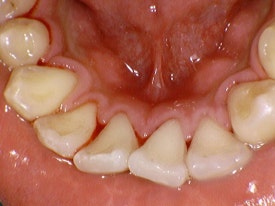

위 사진은 본원에서 진행한 스케일링 전 후 사진입니다.

보기만 해도 너무너무 시원하죠!